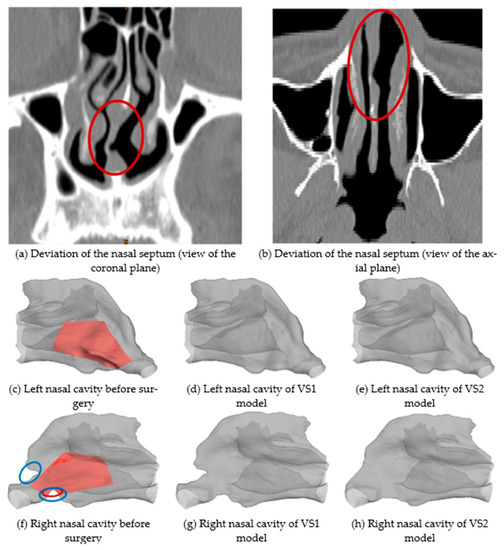

3.1. Airflow Characteristics

3.2. Particle Deposition Fractions (DFs)

3.3. Localized Deposition Patterns